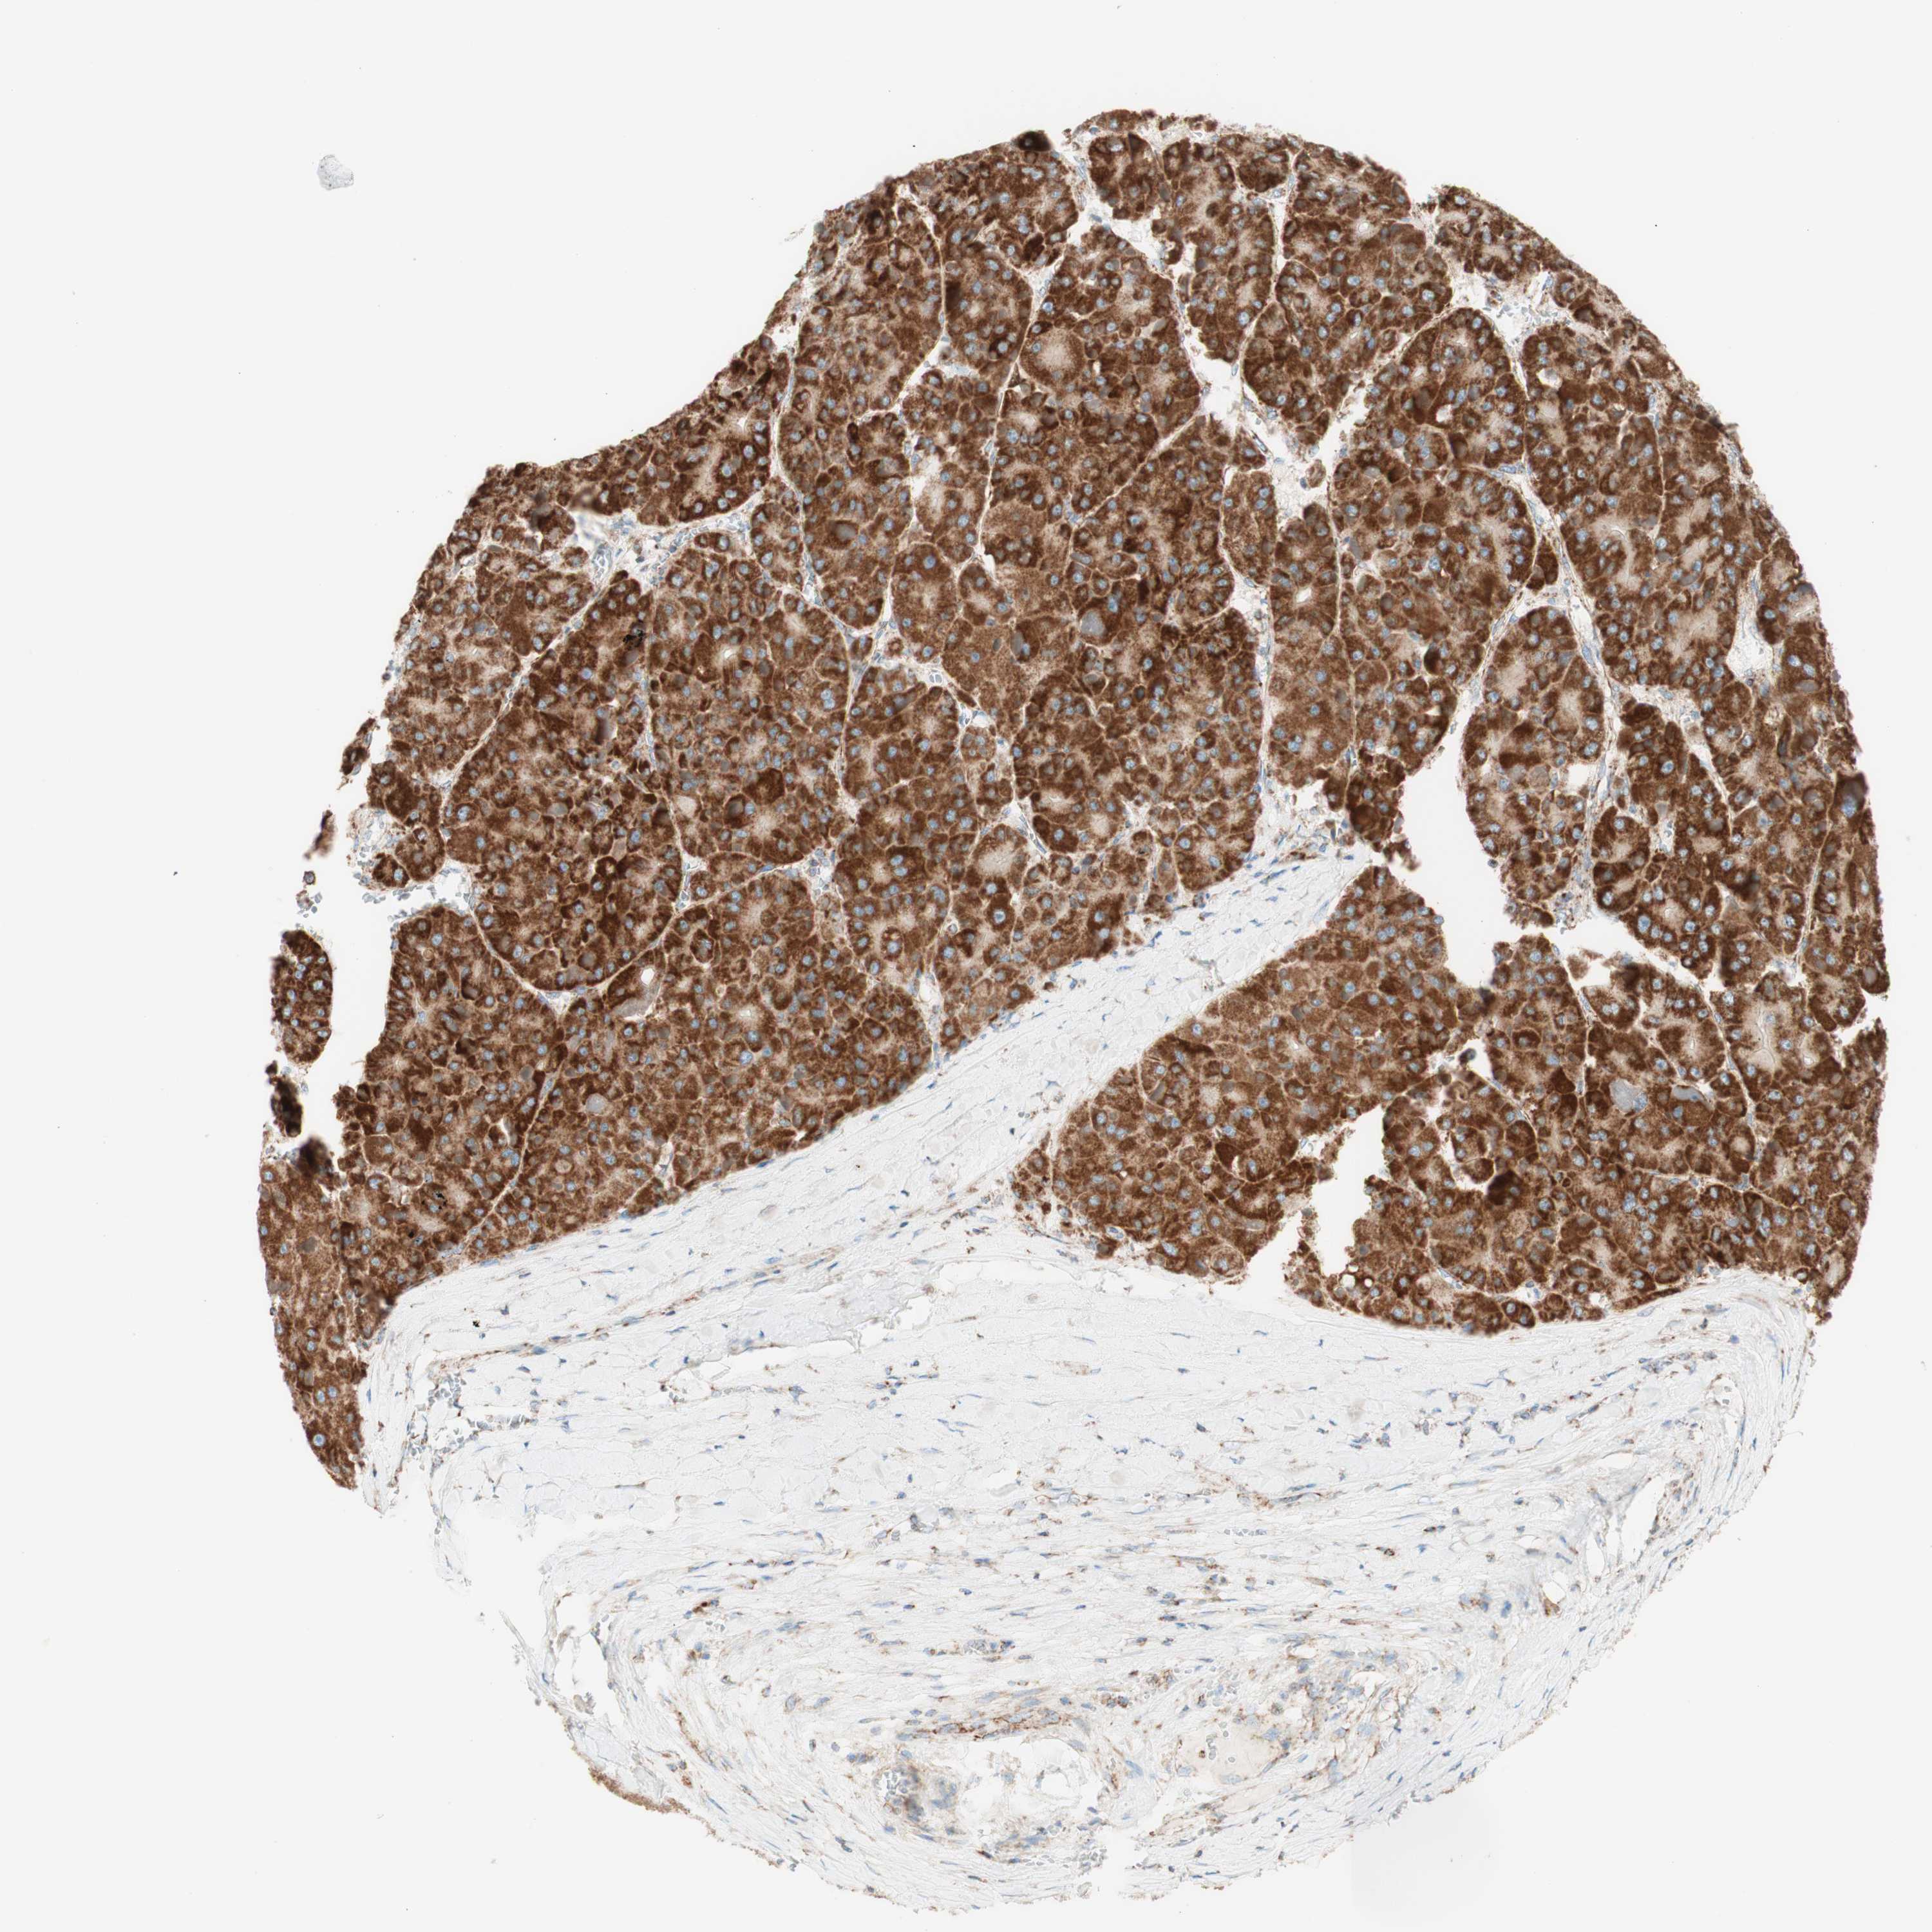

LIVER CANCER - Protein expressioni

A mouse-over function shows sample information and annotation data. Click on an image to view it in a full screen mode. Samples can be filtered based on level of antibody staining by selecting one or several of the following categories: high, medium, low and not detected. The assay and annotation is described here.

Note that samples used for immunohistochemistry by the Human Protein Atlas do not correspond to samples in the TCGA dataset.

Antibody stainingi

Antibody staining in the annotated cell types in the current human tissue is reported as not detected, low, medium, or high, based on conventional immunohistochemistry profiling in selected tissues. This score is based on the combination of the staining intensity and fraction of stained cells.

Each image is clickable and will lead to virtual microscopy that enables deeper exploration of all samples and also displays staining intensity scores, fraction scores and subcellular localization as well as patient and tissue information for each sample.

Antibody HPA011562

Antibody CAB005585

Staining

High

Medium

Low

Not detected

Intensity

Strong

Moderate

Weak

Negative

Quantity

>75%

75%-25%

<25%

None

Location

Nuclear

Cytoplasmic/membranous

Cytoplasmic/membranous,nuclear

Cholangiocarcinoma

Carcinoma, Hepatocellular, NOS